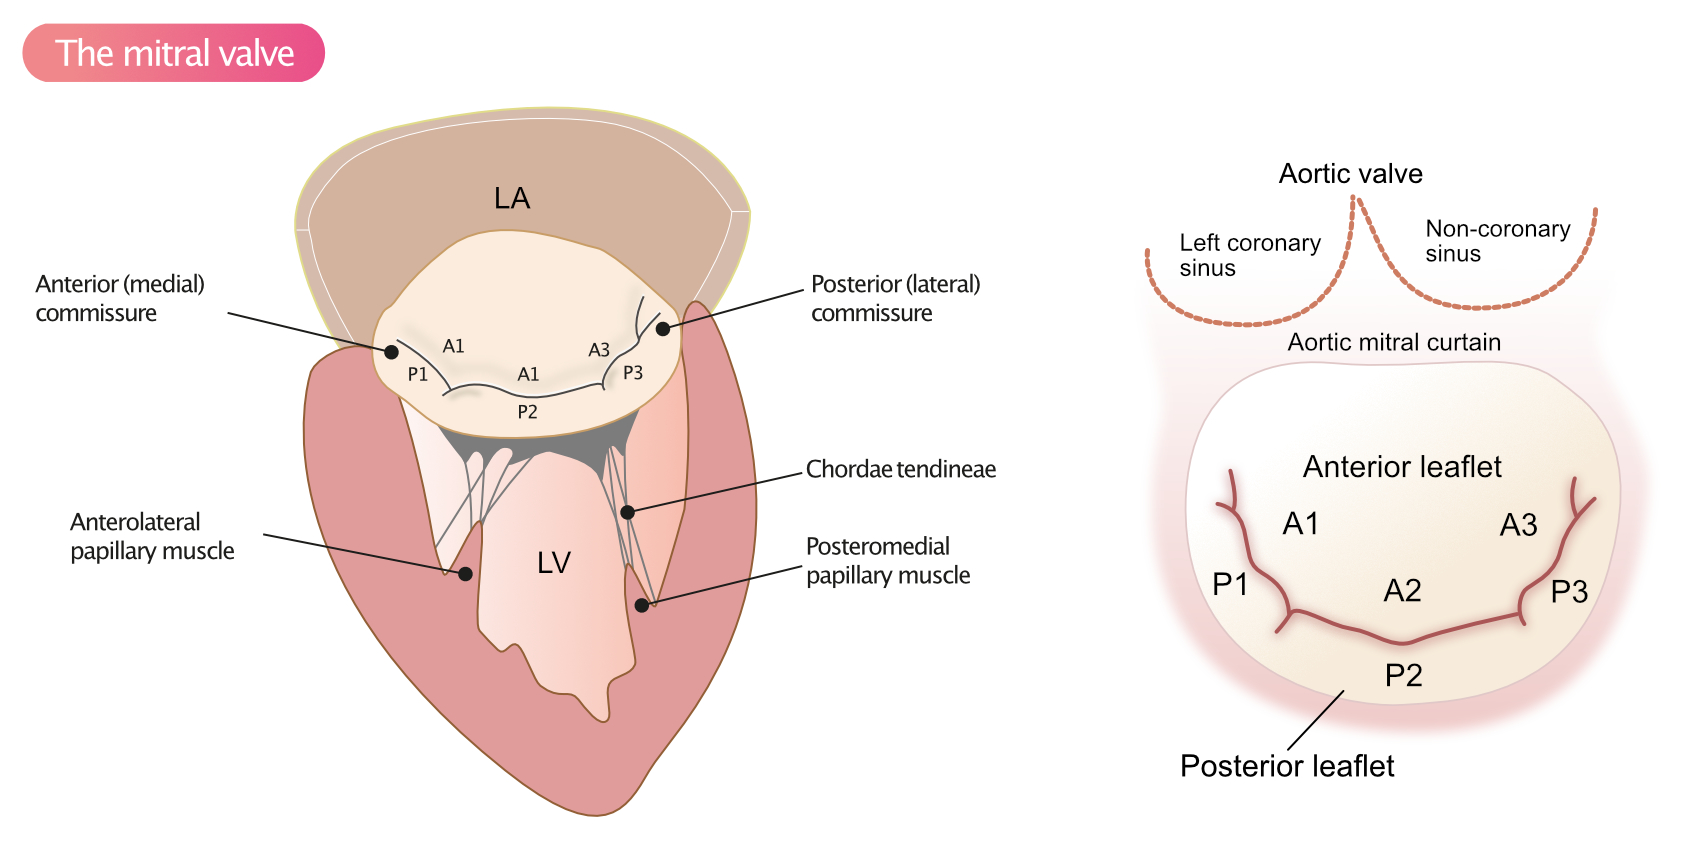

Mitral Valve Basal Chordae: Comparative Anatomy And Terminology - The

www.annalsthoracicsurgery.org

www.annalsthoracicsurgery.org

basal chordae mitral valve anatomy comparative terminology

Mitral Valve Stenosis - Echocardiography, Diagnosis, Causes, Severity

ecgwaves.com

ecgwaves.com

mitral regurgitation stenosis echocardiography chordae tendineae echo ecg anterior papillary medial rupture scallops scallop ekg ecgwaves congenital riss